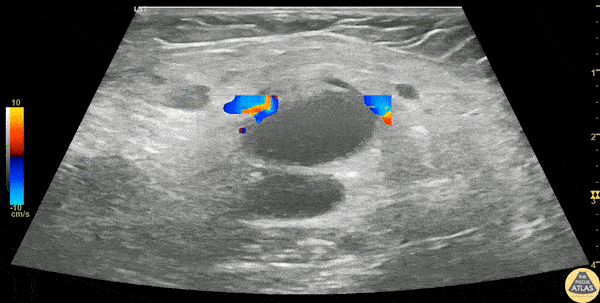

A 30s F presented with L groin pain and swelling. On exam she had pain and focal soft tissue swelling over her inguinal crease. POCUS was performed which demonstrated this enlarged lymph node, suggesting lymphadenitis. In this clip, the lymph node is shown using color doppler, which shows a small amount of flow at the lymph node hilum, without other areas of flow in the node. In the last part of the clip, compression with the probe does not change the shape of the node, differentiating it from an abscess or cyst. This patient was treated symptomatically and discharged with outpatient follow up of her lymphadenitis. Dr. Stephen Wolf Denver Health Medical Center